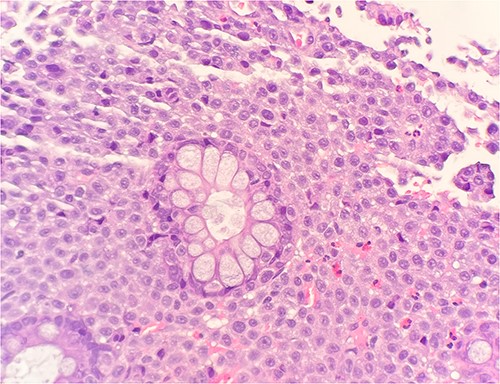

Microscopic examination shows extensive involvement of the bladder wall by sheets of small round blue tumor cells showing cleaved and irregular nuclear contours and conspicuous nucleoli. Mitotic activity is frequent and majority of cells show scant amphophilic cytoplasm with few foci showing more abundant bubbly cytoplasm and others with clear foamy cytoplasm (Fig. 1). A rare foci of finely granular brown pigment representing melanin and moderate cytological atypia in a small area of surface urothelium. Similar morphological features are seen in colonic biopsy specimens (Fig. 2).

Microscopic examination reveals sheets of round cell beneath unremarkable urothelium epithelium. H&E stain 40×.